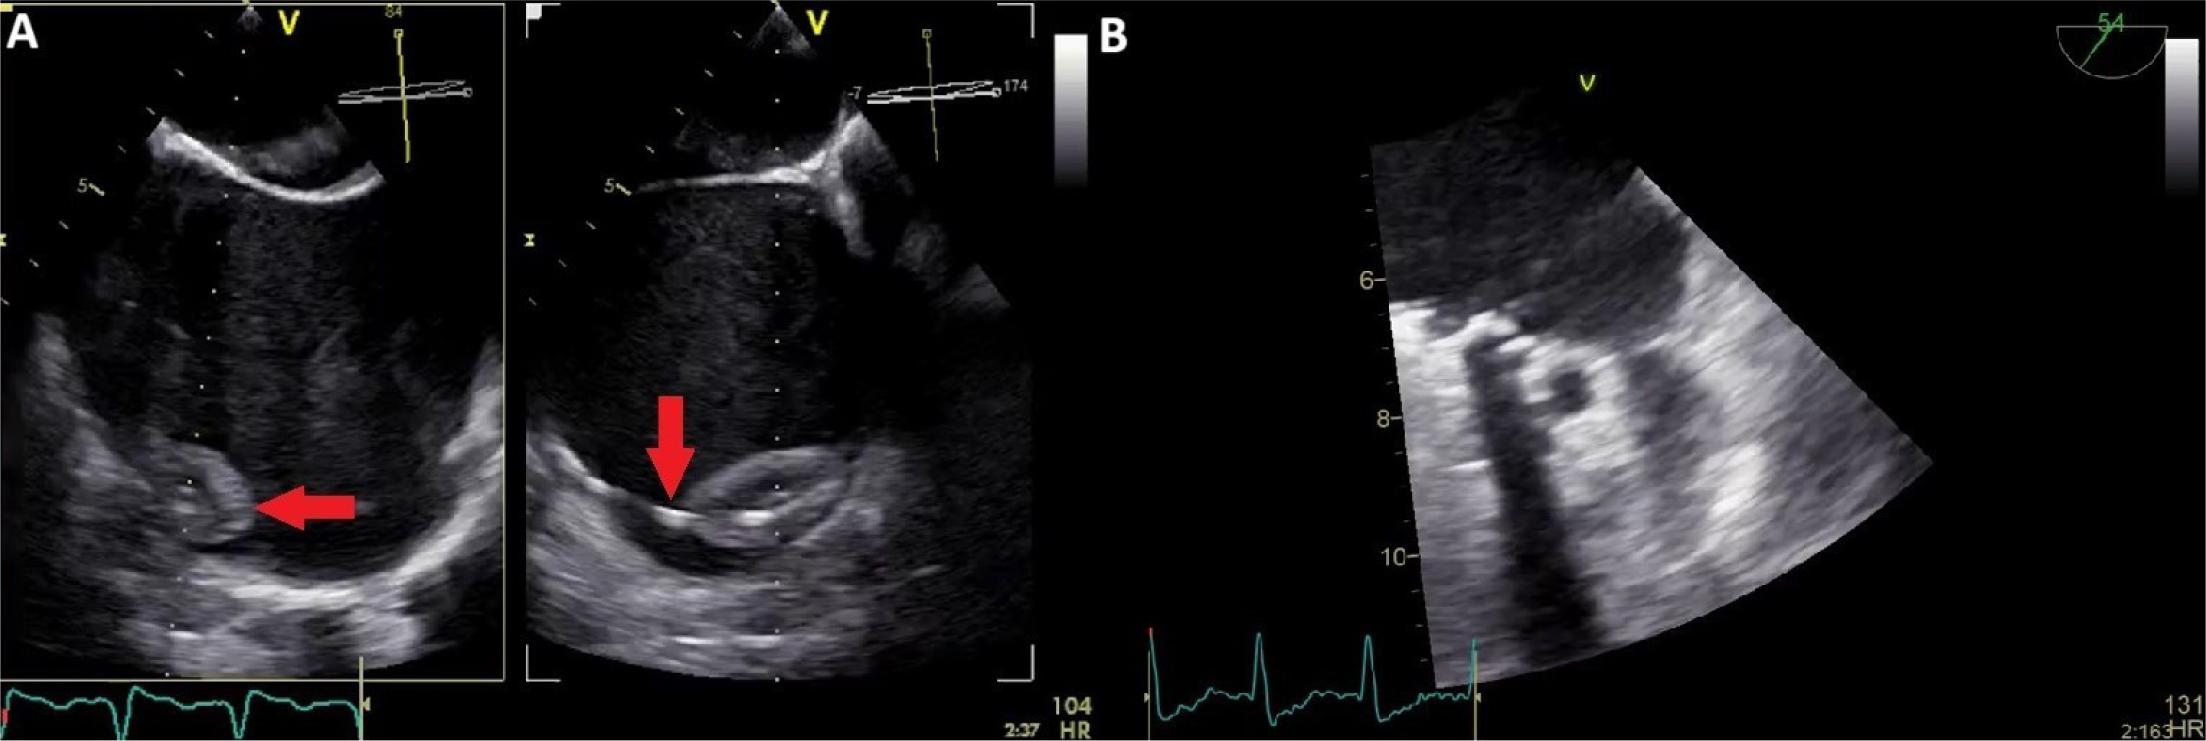

In 2014, the patient’s condition worsened due to an episode of aggravated heart failure. A TTE performed at that time revealed an immobile leaflet and severe obstruction of the tricuspid prosthesis. A comprehensive evaluation was conducted using multiple imaging modalities including transoesophageal echocardiography (TOE) and cinefluoroscopy in addition to TTE, which identified the underlying cause of the obstruction: both pannus and a small thrombus causing blockage of the lateral leaflet in a partially open position, in a patient already known with significant PPM (Figure 1). TOE images also revealed thrombosis of the pacing lead and in the left atrial appendage (LAA) (Figure 2).

Transoesophageal echocardiography. A) Pacing lead thrombosis (red arrow). B) Left atrial appendage thrombosis.